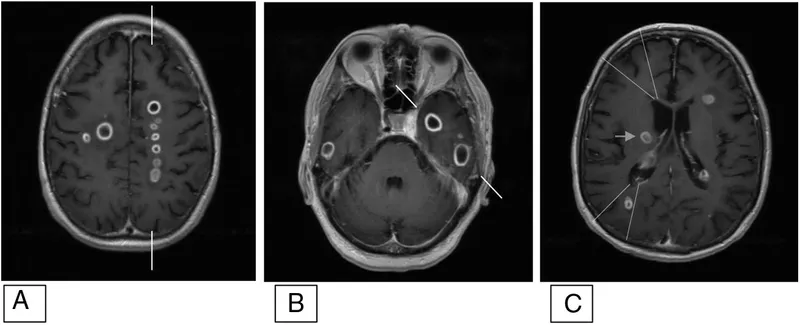

- MRI Brain + MRV (Gadolinium): Gold standard for defining extent, type (abscess, meningitis, DVST).

⭐ MRI with gadolinium contrast is the gold standard for suspected intracranial complications of sinusitis.

- CECT is initial imaging; MRI with gadolinium is gold standard for diagnosis.